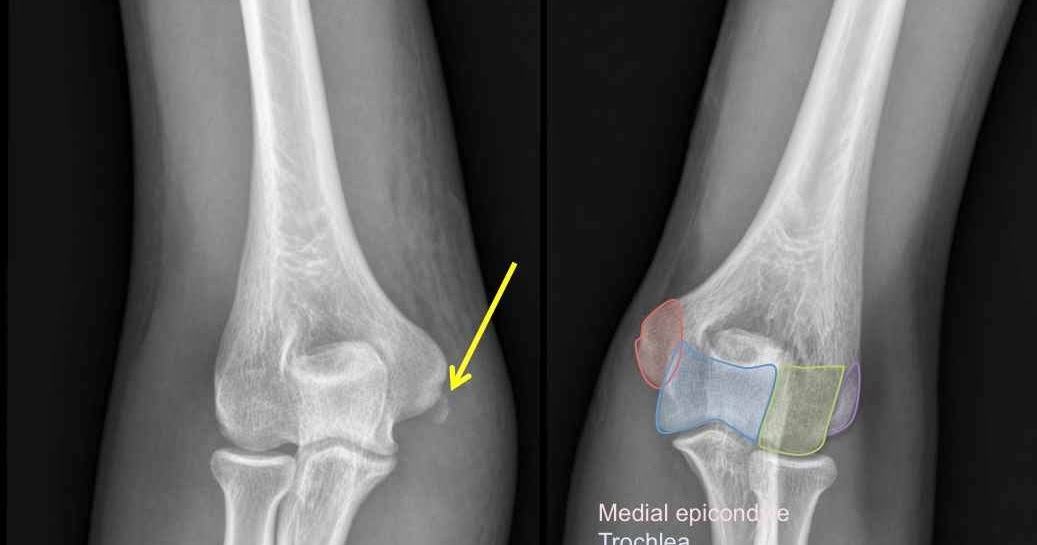

A 52-year-old male with Hoffa fracture of the medial ...

A 52-year-old male with Hoffa fracture of the medial ... from www.researchgate.net

Treatment of partial articular fracture, medial condyle. Contraindications to sw treatment (infection or cancer. Medial condyle fractures are intraarticular, extending into the elbow joint and require urgent open reduction internal fixation (orif). Posterior femoral line (white) c. Used for complex medial femoral condyle fractures. Femoral neck fractures in the elderly are frequent, represent a great health care problem, and have a significant impact on health insurance costs. Femoral neck fractures carol lin, md & brad merk, md original authors: This case report describes a periprosthetic fracture of the medial femoral condyle that occurred during an oukr. The distal end of the femur has medial and lateral condyles. Medial femoral condyle fracture kneeall software. In neglected hoffa fractures despite nonunion, there is a risk of missing we help you select the appropriate treatment of partial articular fracture, medial condyle, sagittal simple located in our module on distal femur. Implantation of bipolar prosthesis for treatment of medial femoral neck fractures in the elderly. For simple fractures of the medial condyle, a medial parapatellar surgical approach is most commonly used. Keywords femur á medial condyle fracture á nonunion á retrograde intramedullary nail. Treatment of distal femur fractures. .between medial and lateral vastus muscles causing impingement of the superolateral aspect of hoffa fat pad between the inferior patella and the lateral femoral condyle. Medial condyle extends more distal than lateral condyle.